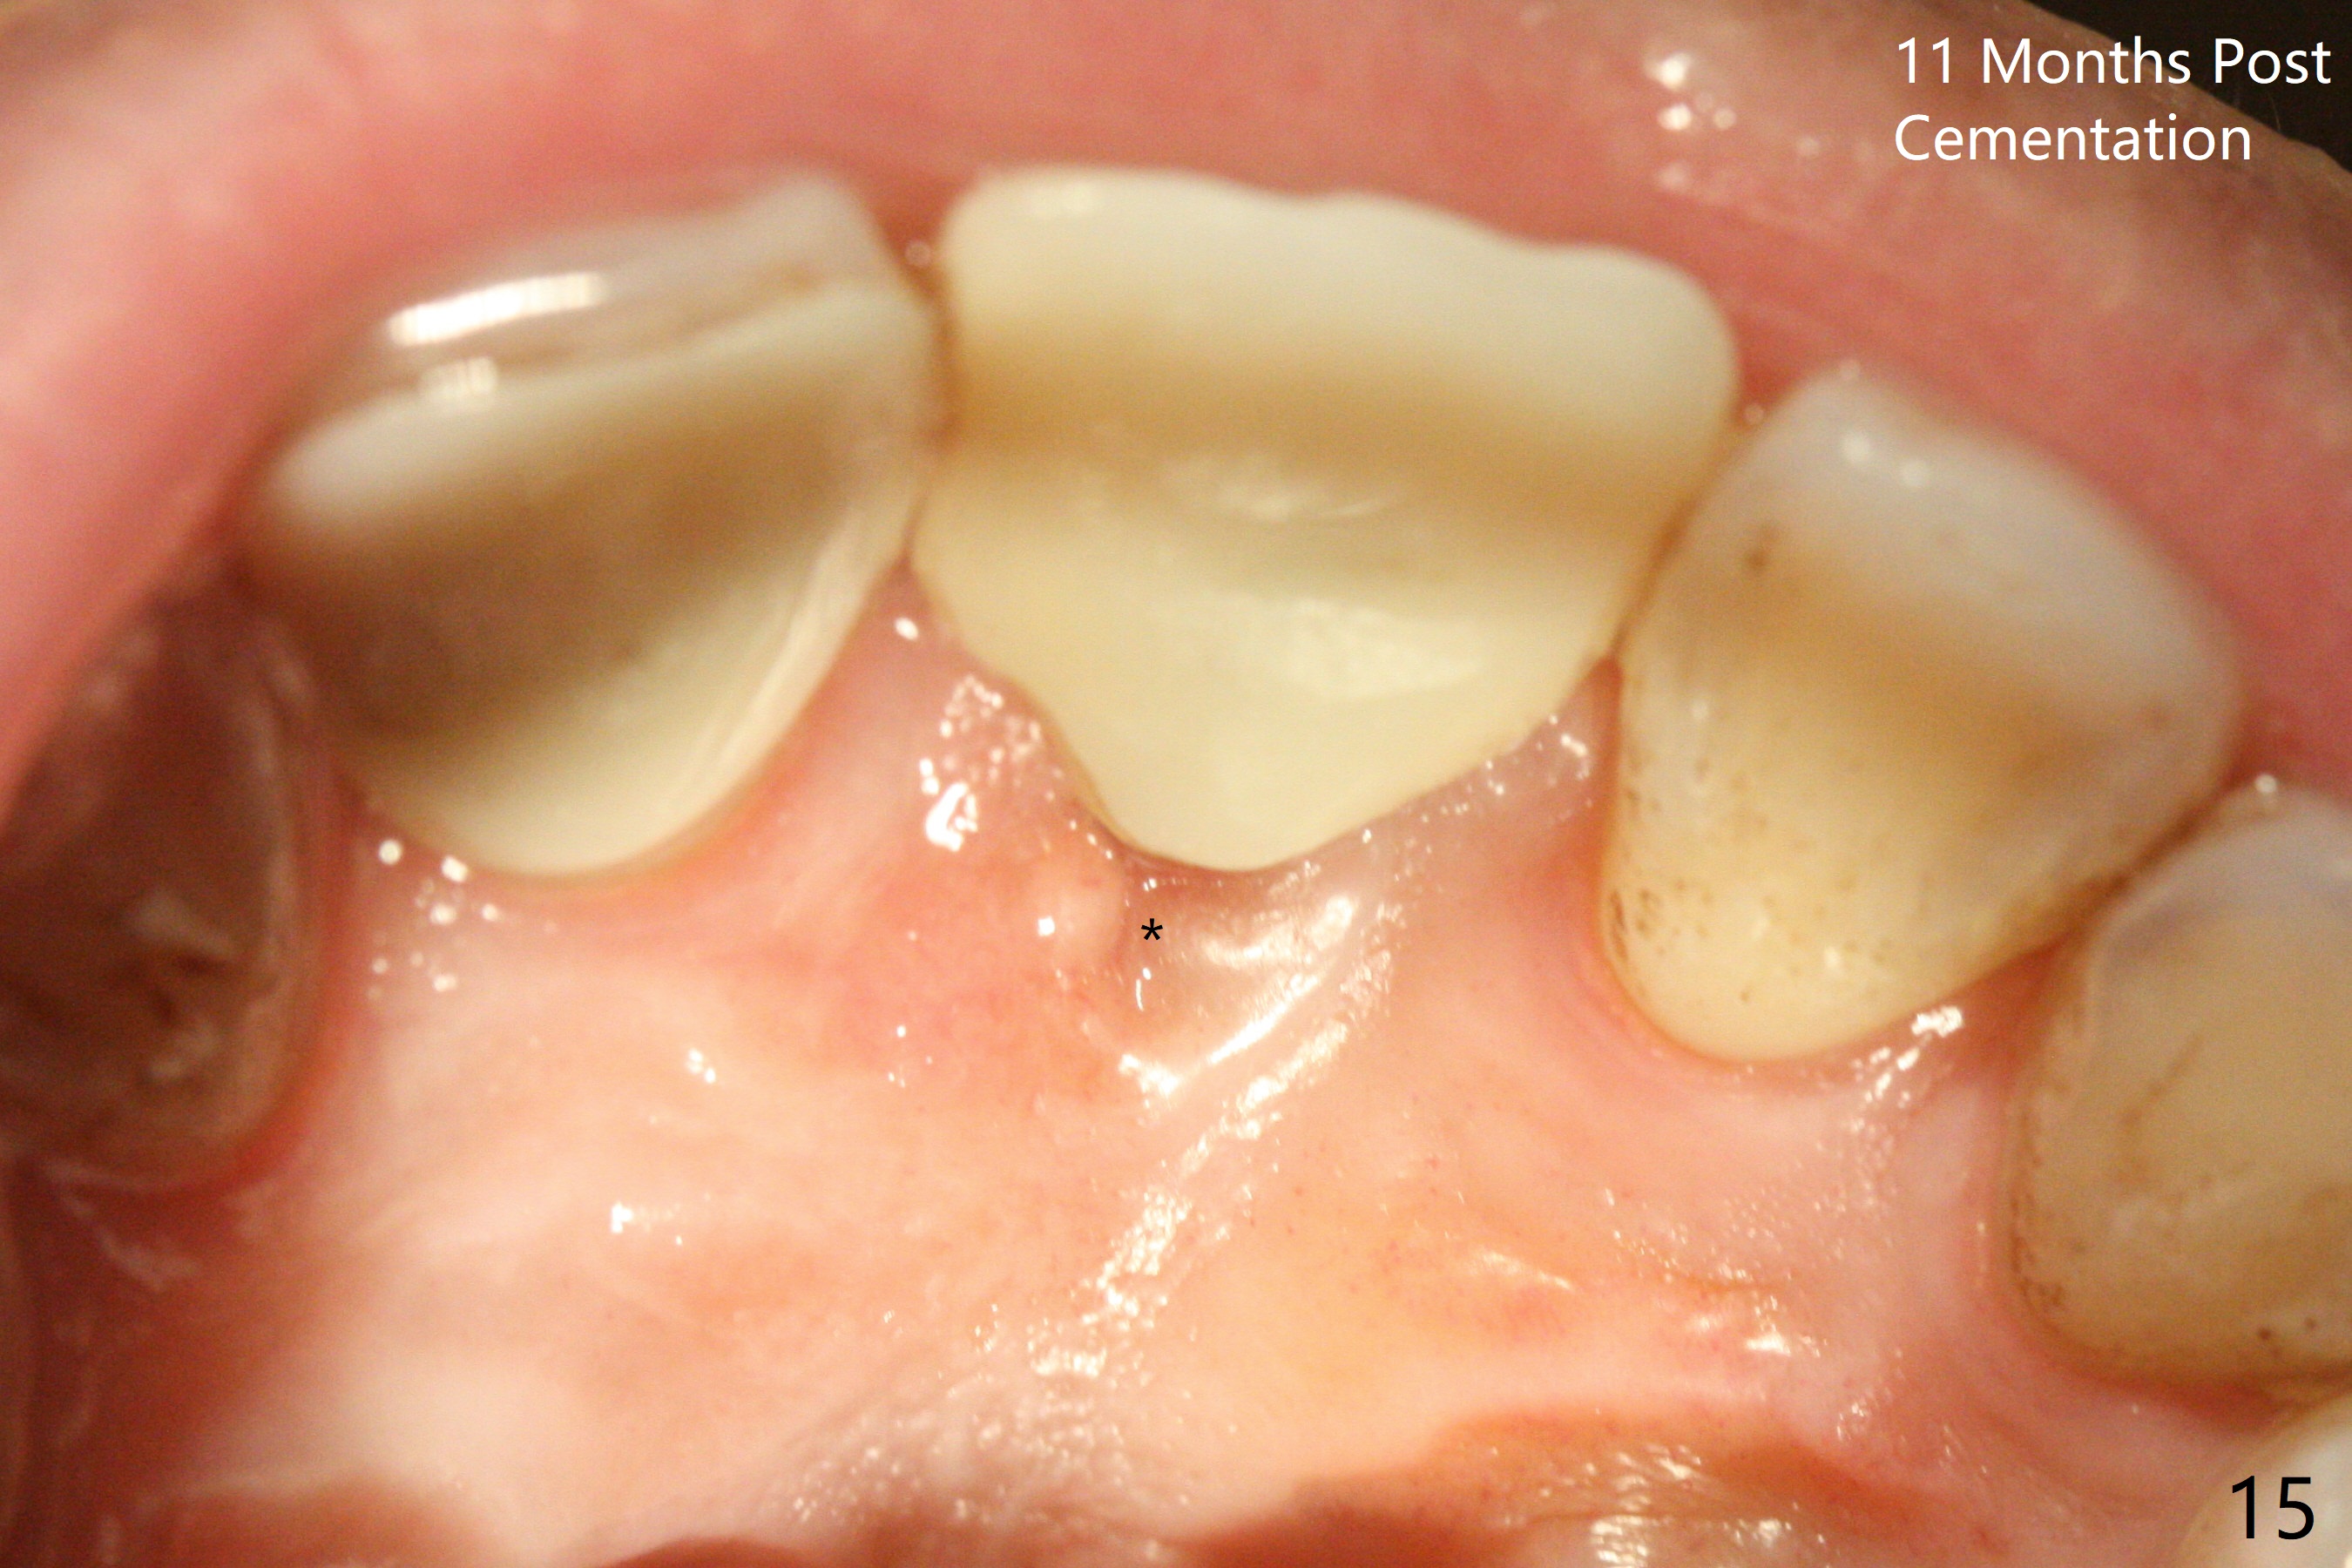

Except the depth, a 2.5x10 mm mini implant is placed with precision (in trajectory) at #9 (Fig.1-5). Confidence using surgical guide for the narrow ridge is enhanced due to placement of two digits against the buccal and palatal plates for tactile sensation. The depth issue is related to overprep with 2.2 mm drills. The torque is <15 Ncm. The immediate provisional is bonded to the neighboring teeth for retention. It appears that smaller drills should be made for guided surgery (such as 1.5 and 2.0 mm). The immediate provisional looks acceptable buccal and occlusal 3 weeks postop (Fig.6,7), although the palatal gingiva is erythematous (Fig.8, which is common after use of drill for access (tissue laceration), OHI offered). Three months postop (Fig.9), the palatal gingiva looks healthy (data not shown), while there is no bone loss around the implant (Fig.10). It remains the same 5 months postop (immediately post cementation, Fig.11) and 3,11 months post cementation (Fig.12,13). The labial gingiva is healthy (Fig.14), while the palatal one is less erythematous and edematous (Fig.15) than earlier (Fig.8).